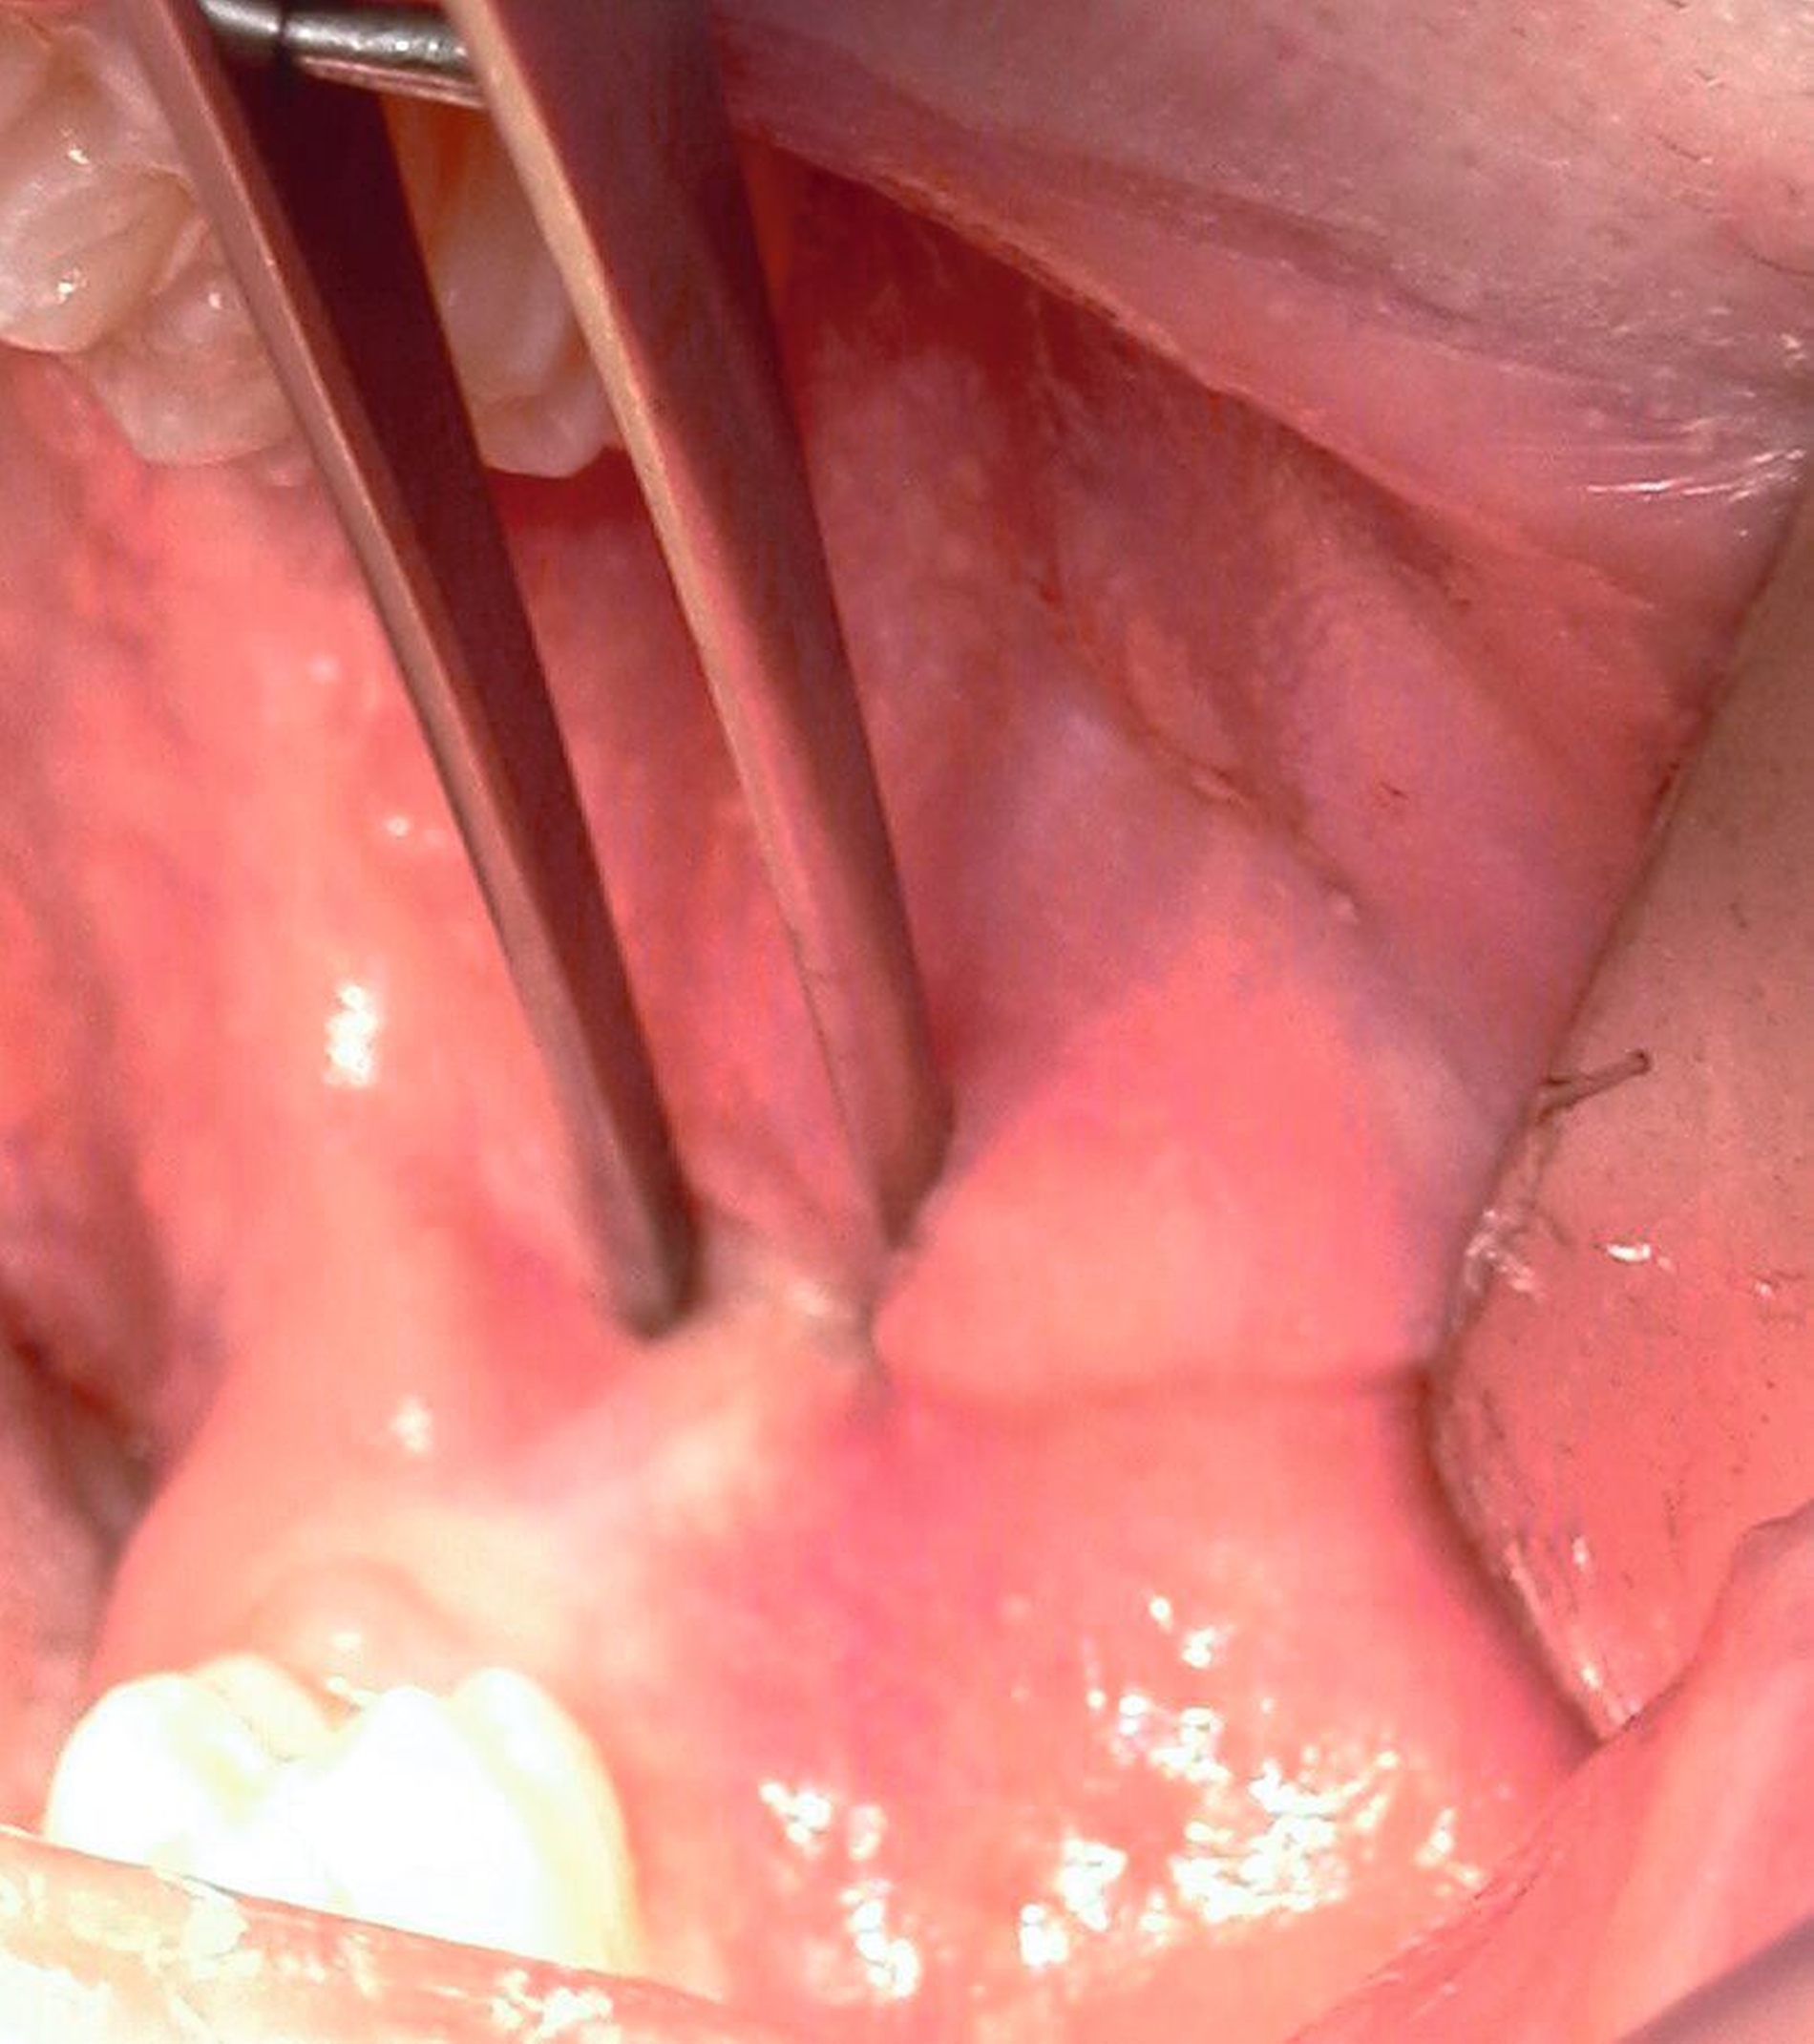

Nach Freilegung des Knochens kann ein Wundhaken nach Langenbeck eingesetzt werden sowie ein Bohr-Raspatorium zum Schutz des N. lingualis subperiostal lingual [Gutwald et al., 2019]. Unter Verwendung eines rotierenden Instruments (Kugel- und Lindemann-Fräse) oder Piezochirurgie wird der Knochen im Bereich der Zahnkrone abgetragen und diese freigelegt (Abbildung 8). Danach kann der Weisheitszahn vorsichtig mithilfe eines Bein‘schen Hebels anluxiert oder, falls dies noch nicht gelingt, mittels einer Lindemann-Fräse geteilt werden. Dabei wird am größten Kronendurchmesser die Krone mit der Fräse abgetrennt und die Wurzel anschließend separat entfernt (Abbildungen 9 und 10) [Gutwald et al., 2019; Schwenzer, 2019].

Die Vorgehensweise ähnelt der konventionellen Weisheitszahnentfernung im Unterkiefer. Zunächst wird ein Mukoperiostlappen gebildet und die Zahnkrone freigelegt. An der größten Zirkumferenz wird diese mittels Lindemann-Fräse unter ständiger Wasserkühlung und anschließend mithilfe eines Bein´schen Hebels abgetrennt. Dabei sollte der Wurzelblock nicht anluxiert werden, da er sonst aufgrund eines erhöhten Infektionsrisikos entfernt werden muss. Alle Schmelzanteile werden entfernt, der verbleibende Wurzelblock und die Knochenkanten geglättet (Abbildung 16). Auf eine weitere Behandlung der Wurzelpulpen kann verzichtet werden [Wolf & Renton, 2016].